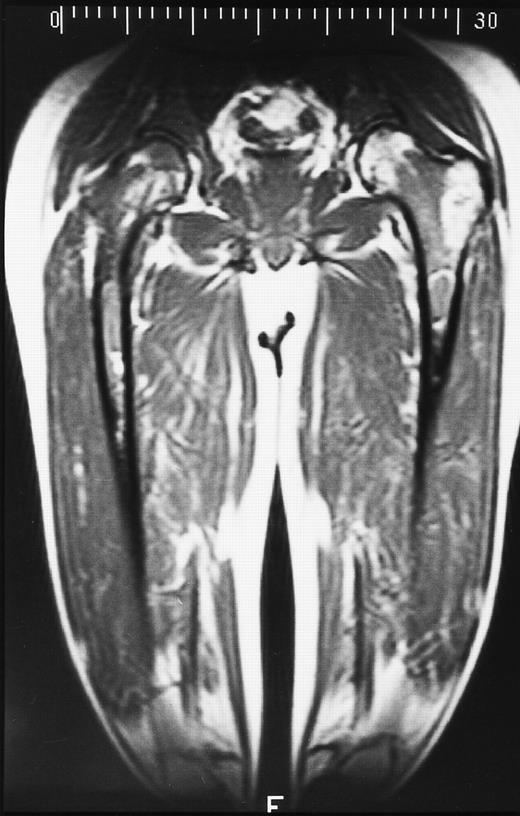

A 28-year-old man treated with 8 courses of neoadjuvant chemotherapy and granulocyte-macrophage colony-stimulating factor for Ewing sarcoma of the right ischium. T1-weighted coronal MR image shows dark signal in the diaphyses of both femoral bones in keeping with reactivation of red marrow in the peripheral skeleton.